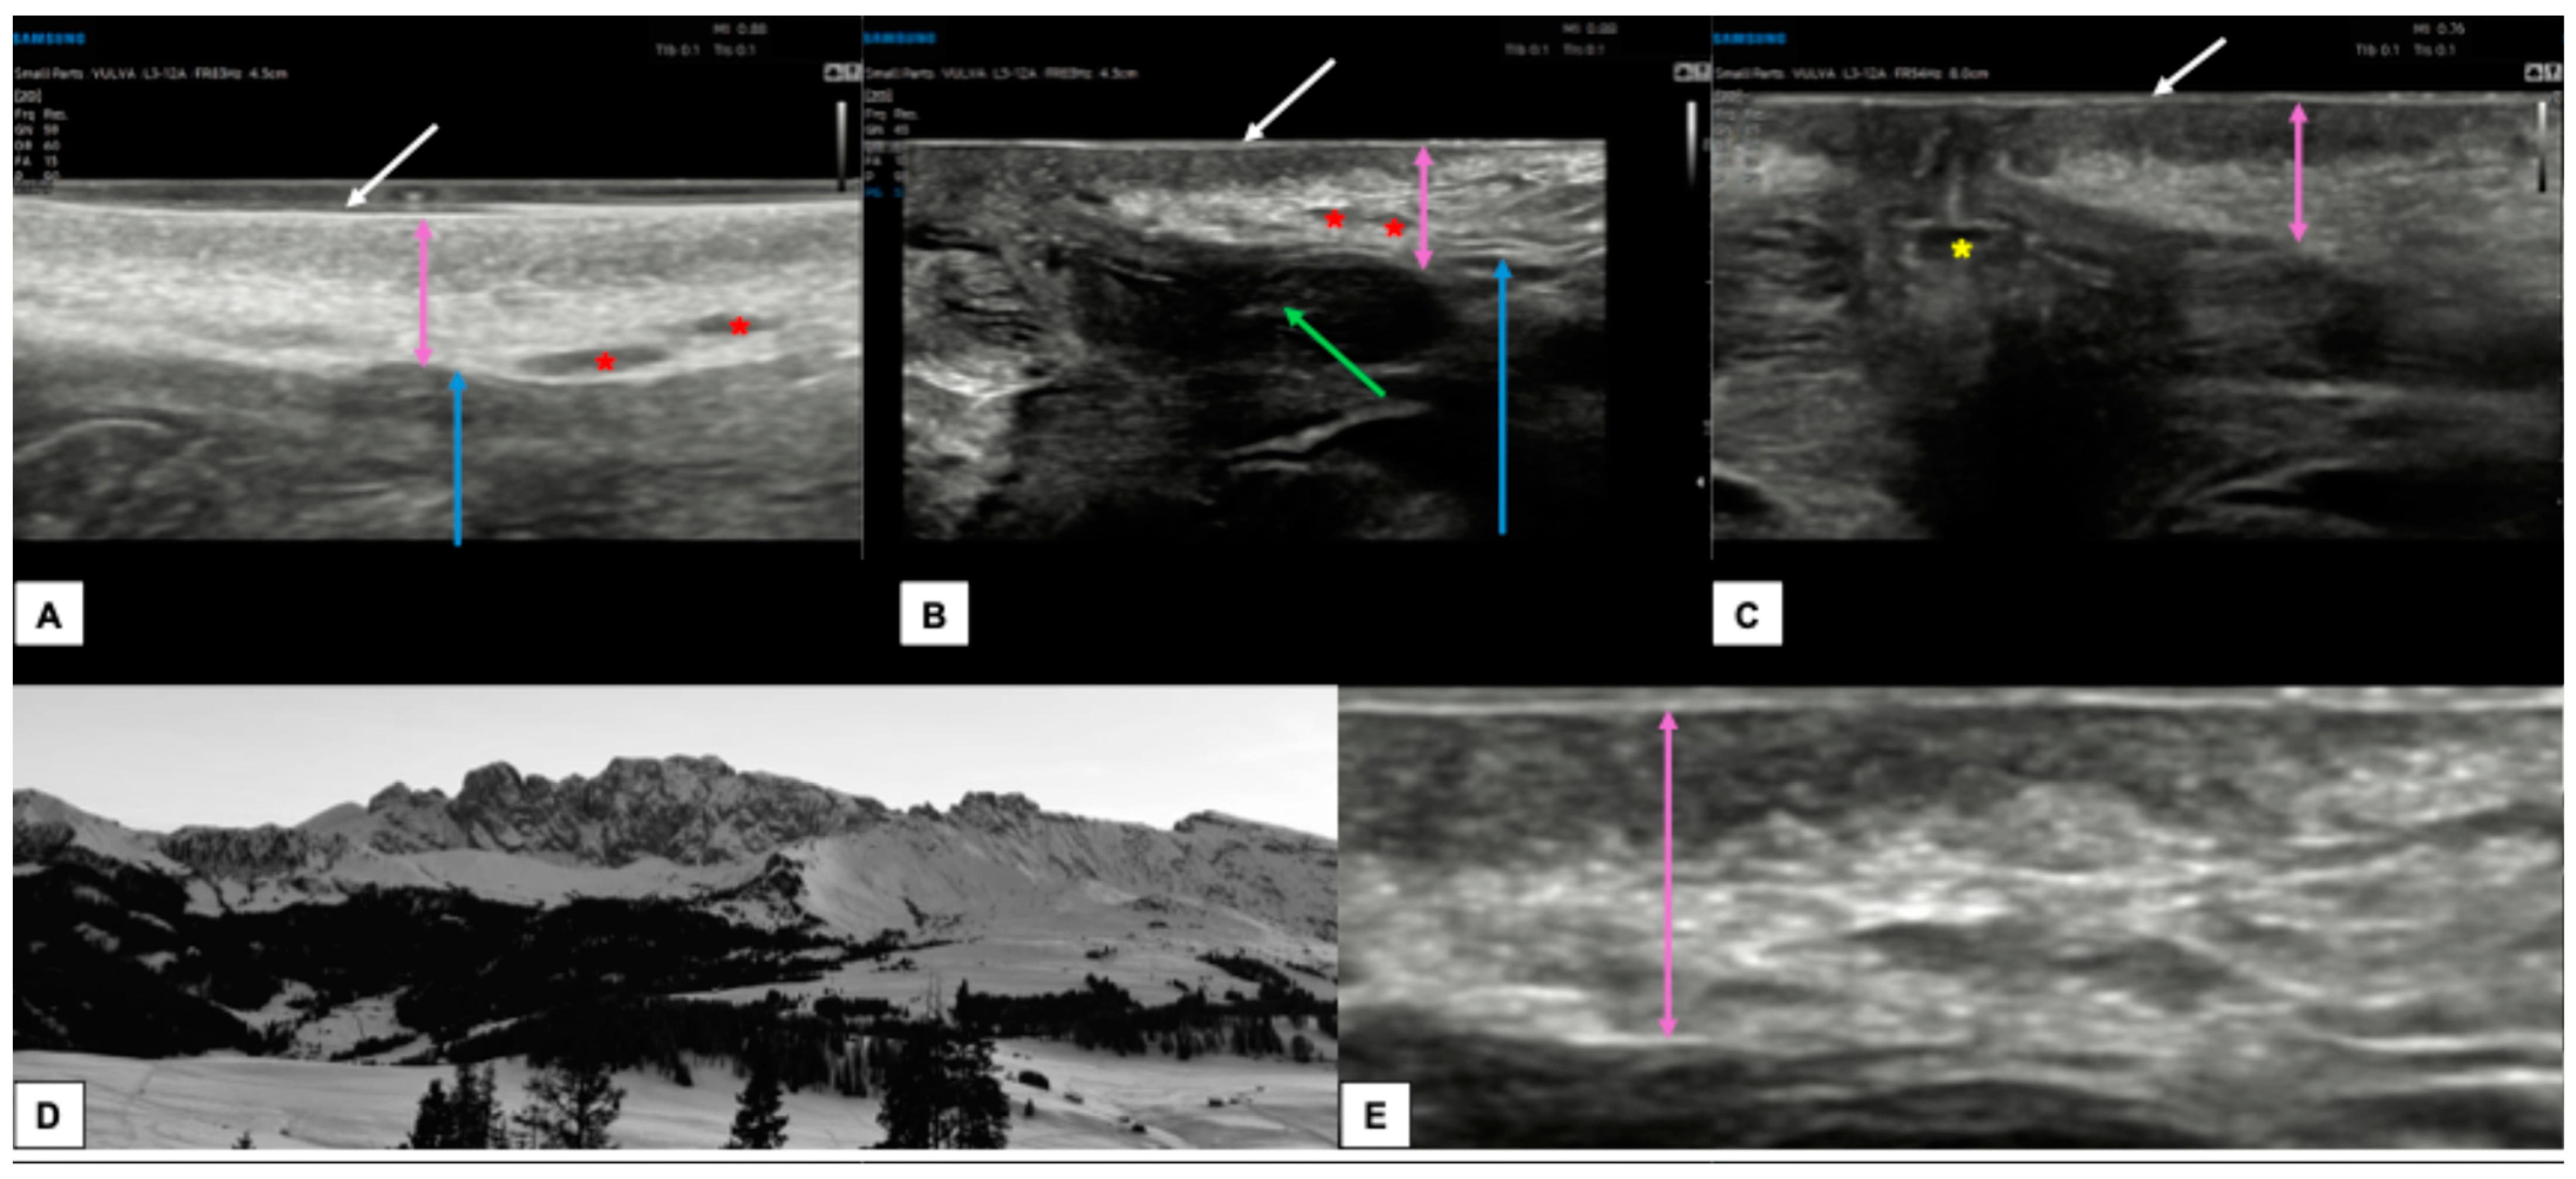

7.3. Malignant Vulvar Lesions

- Measurement from the adjacent most superficial dermal papilla to the deepest point of invasion

- Measurement from the basement membrane of the deepest adjacent dysplastic (tumor-free) rete ridge to the deepest point of invasion, which should be the technique of choice. Because epidermal ridges cannot be distinguished on ultrasonography, our suggestion is to take the lower hyperechogenic line of the epidermal layer as a reference (Figure 10).